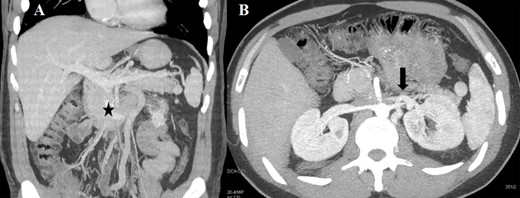

(A) CT scan (coronal section) of the retroperitoneal mass (asterisk) involving the IVC and LRV with congested gonadal vessels; (B) cross-section CT scan showing well-represented collateral outflow (arrow) of the renal–azygos–lumbar system.

Case 1 was a 33-year-old male affected by a right testicular germ-cell tumor with enlarged retroperitoneal lymph nodes surrounding the infrarenal IVC. The patient underwent orchifunicolectomy and subsequent chemotherapy based on bleomycin, etoposide and platinum. A restaging computed tomography (CT) scan showed partial response and confirmed residual tumor involving both the IVC (with occluding thrombus) and the distal left renal vein (LRV) (Fig. 1A). CT scan also showed an efficient venous collateral pathway through the azygos−lumbar system (Fig. 1B), with no clinically evident lower limb edema. The patient underwent an en-bloc resection of the tumor mass with infrarenal IVC and LRV ligation without nephrectomy; no IVC prosthetic replacement was carried out. Recovery from surgery was uneventful with the exception of transient mild renal failure treated conservatively and without the need for dialysis. Renal ultrasonography showed regular bilateral parenchymal perfusion, and doppler ultrasonography of the lower limbs confirmed normal superficial and deep venous outflow. The patient was discharged 9 days after surgery. Histology showed a teratoma with alpha-fetoprotein expression and extensive post-chemotherapy areas of necrosis.